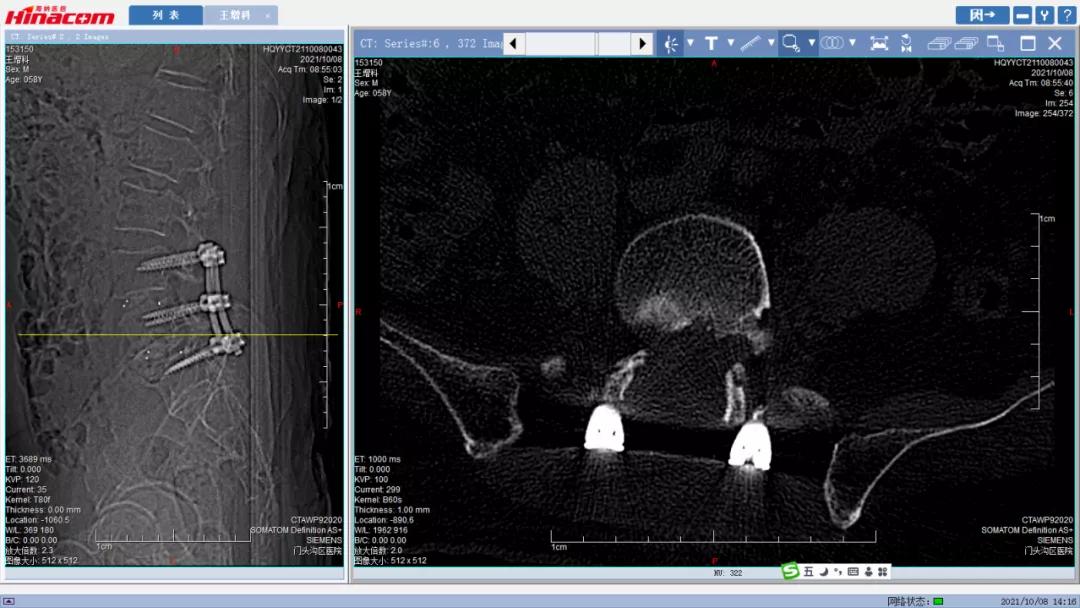

腰45椎间盘--术前CT